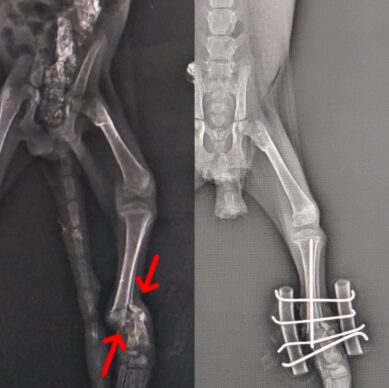

Kedi